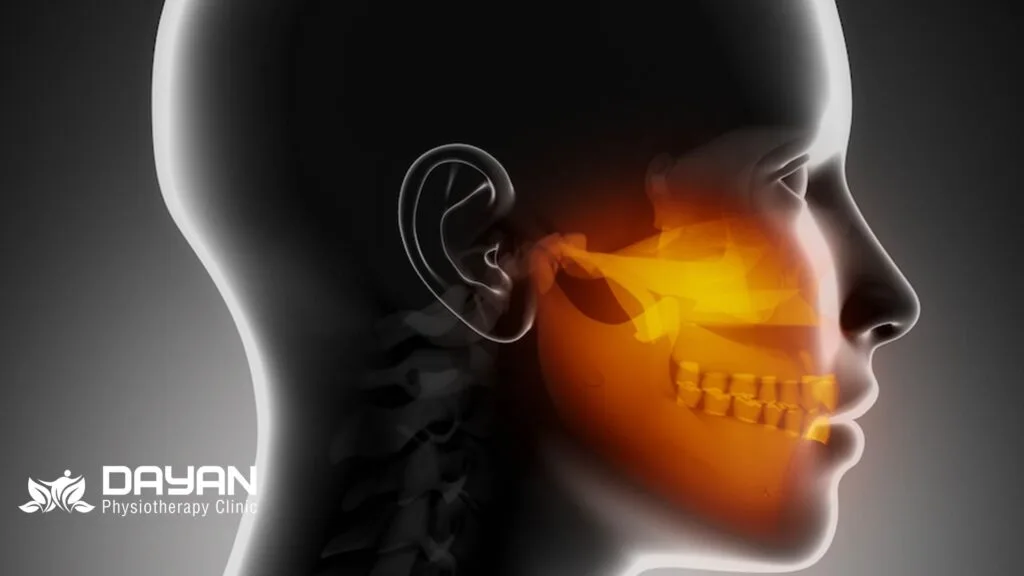

چگونگی درمان سفتی فک صورت سؤال رایجی است که بیماران در کلینیک فیزیوتراپی دایان از ما می پرسند. سفتی و درد فک وضعیتی ناتوان کننده است که بر حرکت گردن، غذا خوردن و صحبت کردن تأثیر می گذارد.

این سفتی در برخی موارد نیز منجر به قفل شدن فک می شود. شدت درد فک متفاوت بوده و اغلب به صورت دردی ضربان دار یا سوزشی احساس می شود.

این علائم با لبخند زدن، صحبت کردن، جویدن یا خمیازه کشیدن تشدید می شوند. همچنین محل درد فک از هر دو طرف فک گرفته تا درست زیر گوش، نزدیک به چانه، گردن یا بینی متفاوت است.

سفتی فک به دلایل رایج و مختلفی از جمله اختلال مفصل فکی گیجگاهی، دندان قروچه، منقبض کردن فک، موقعیت بد گردن، استرس و جویدن بیش از حد ایجاد می شود.

متخصصان فیزیوتراپی ما در کلینیک دایان در جلسه معاینه چگونگی کاهش سفتی و درد فک را برای شما توضیح داده و با هدف قرار دادن عضلات تشکیل دهنده مفصل فکی گیجگاهی از جمله ماستر و تمپورومندیبولار به رفع علائم کمک می کنند.